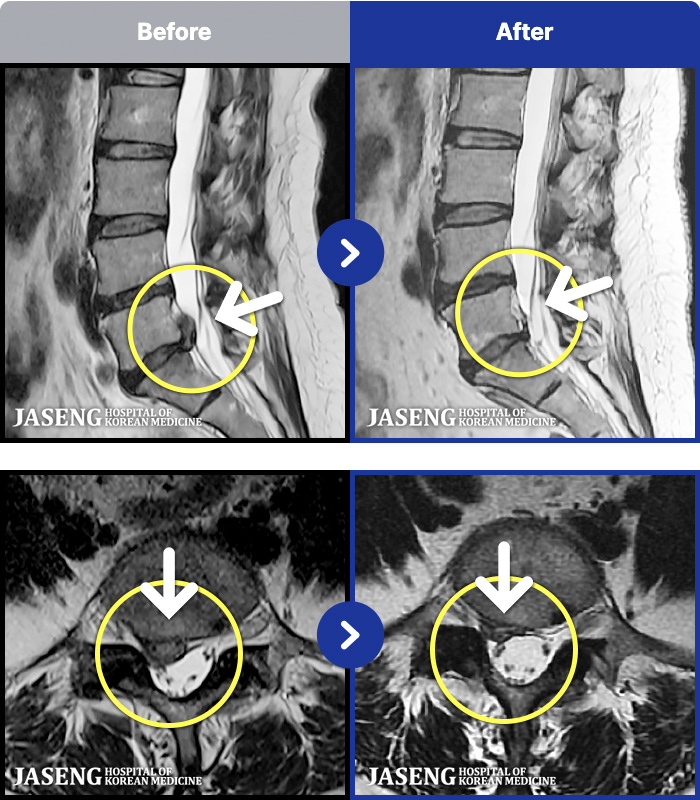

1,268 MRI ũ ʸ Ȯϼ.